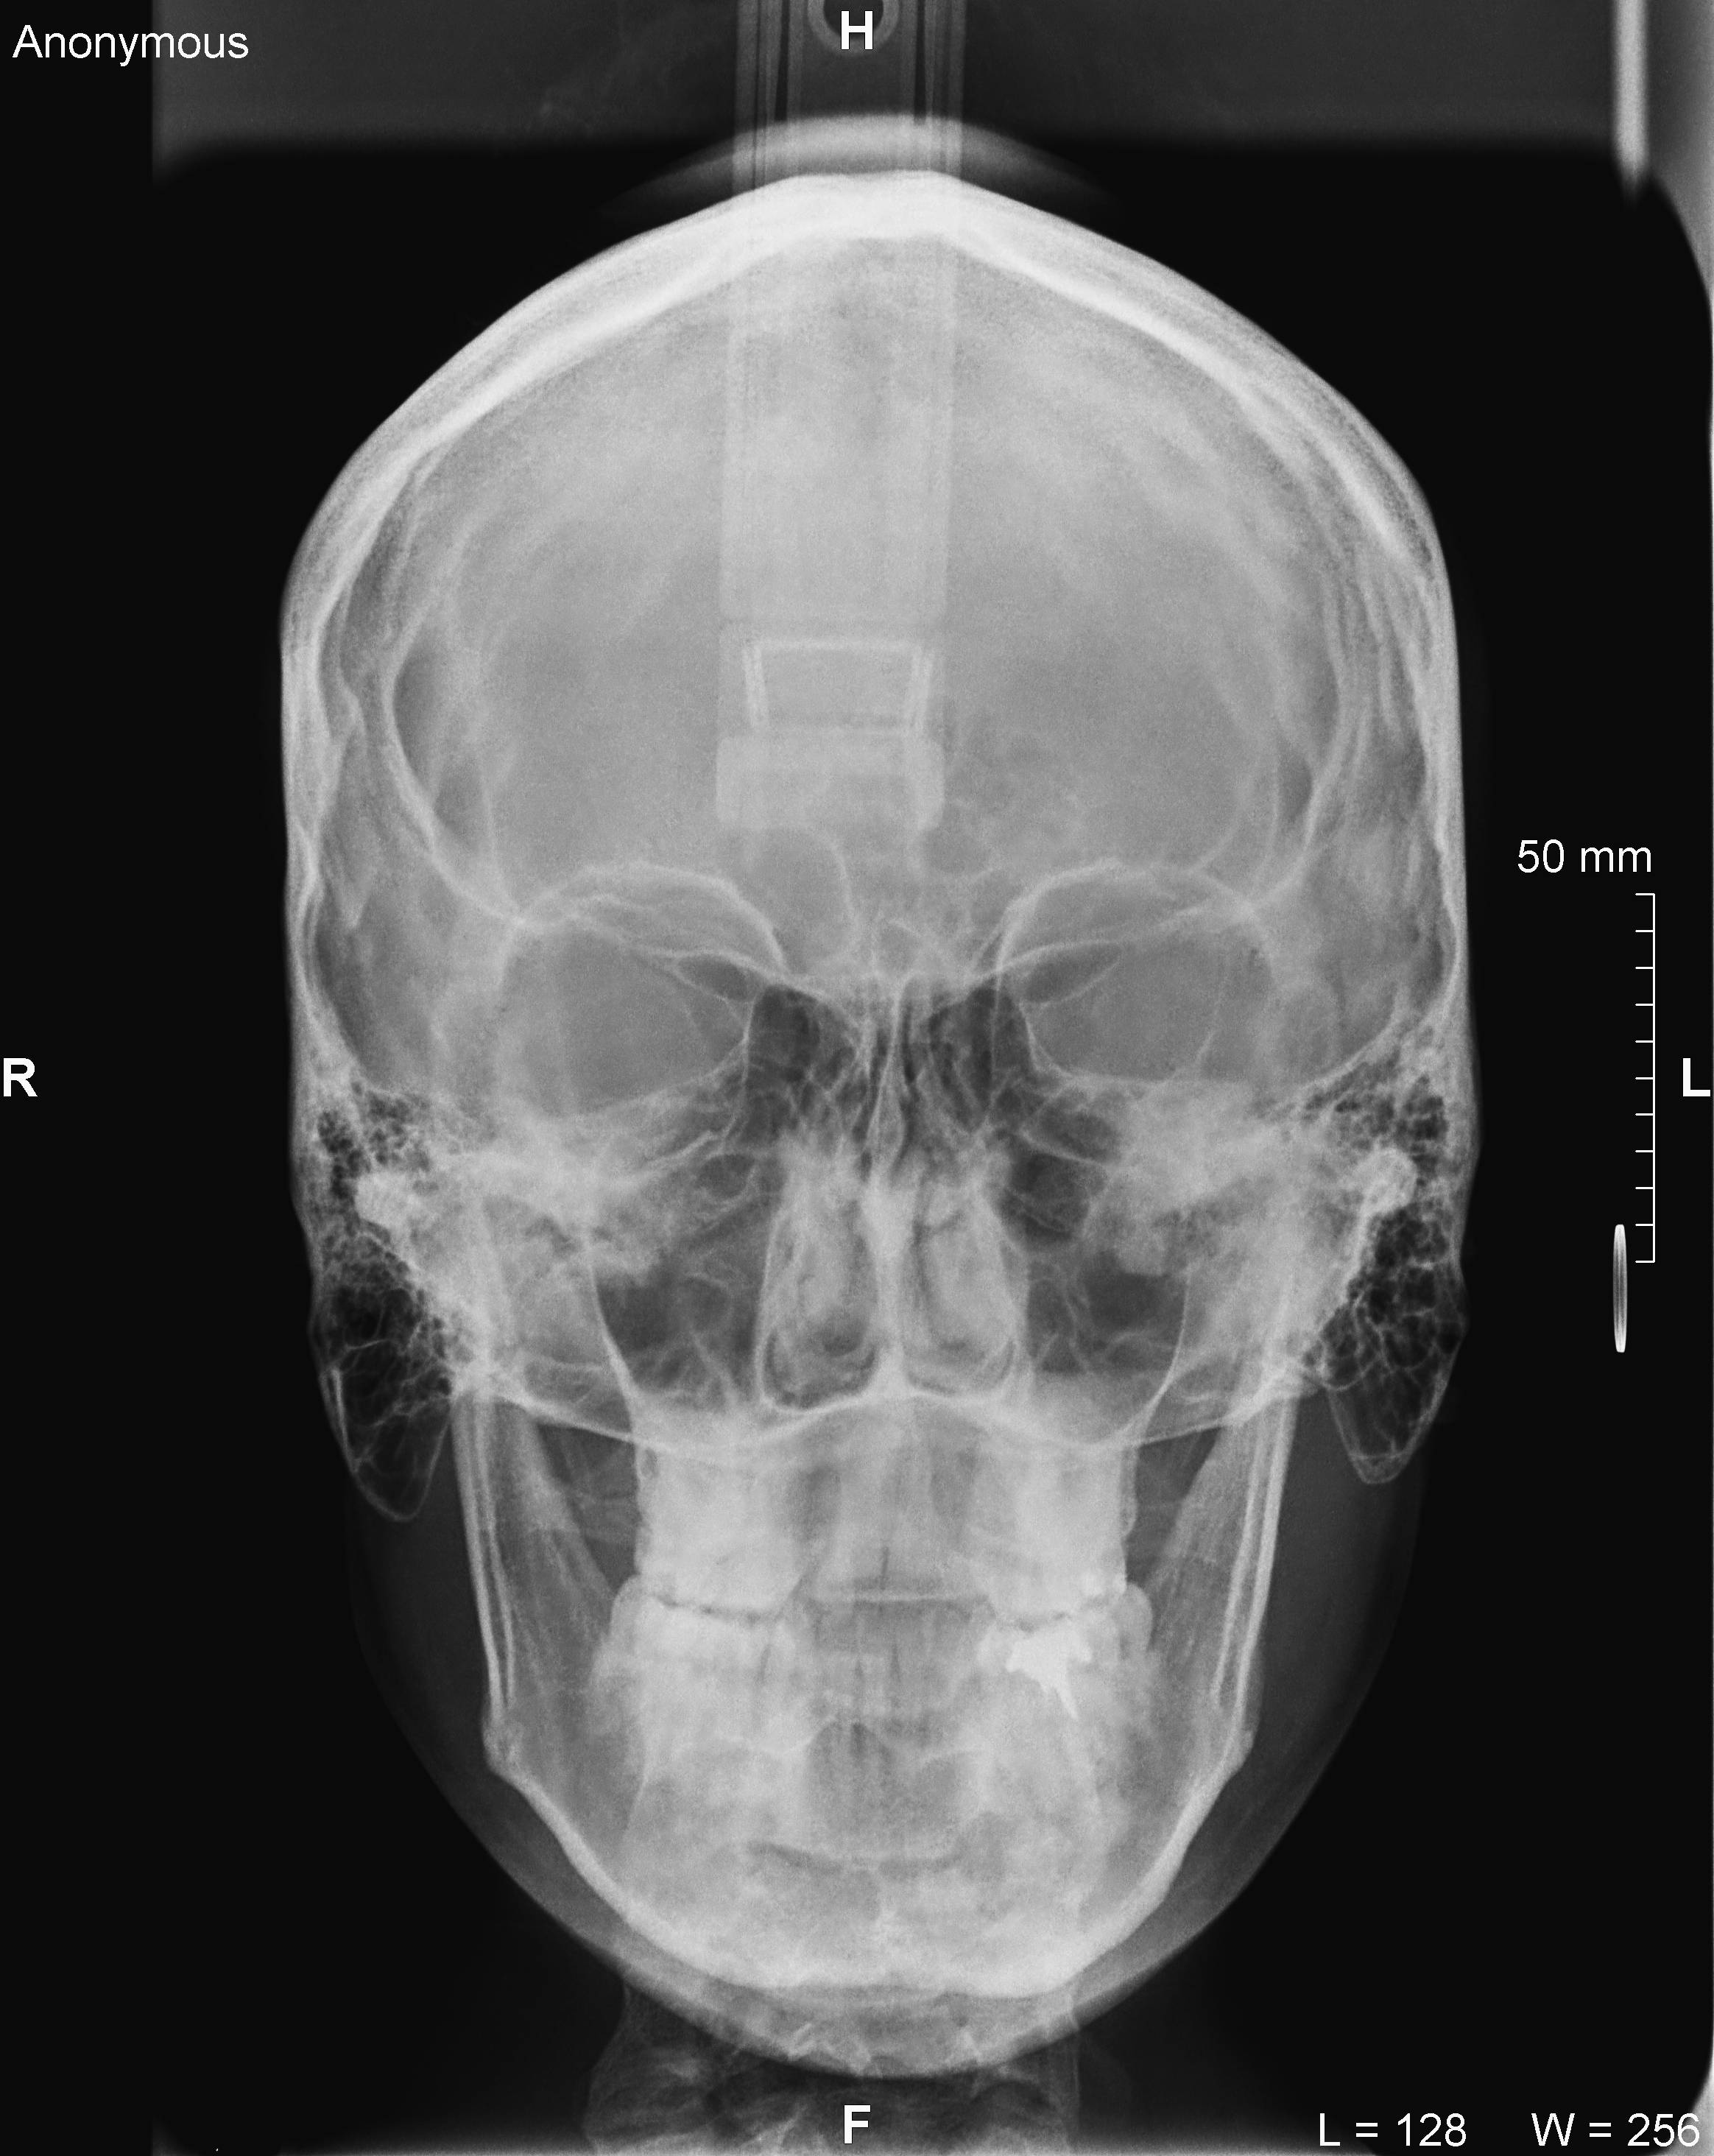

Algunos ejemplos de imágenes digitales

Pulse en las imágenes para ver la ampliación

14fte 1